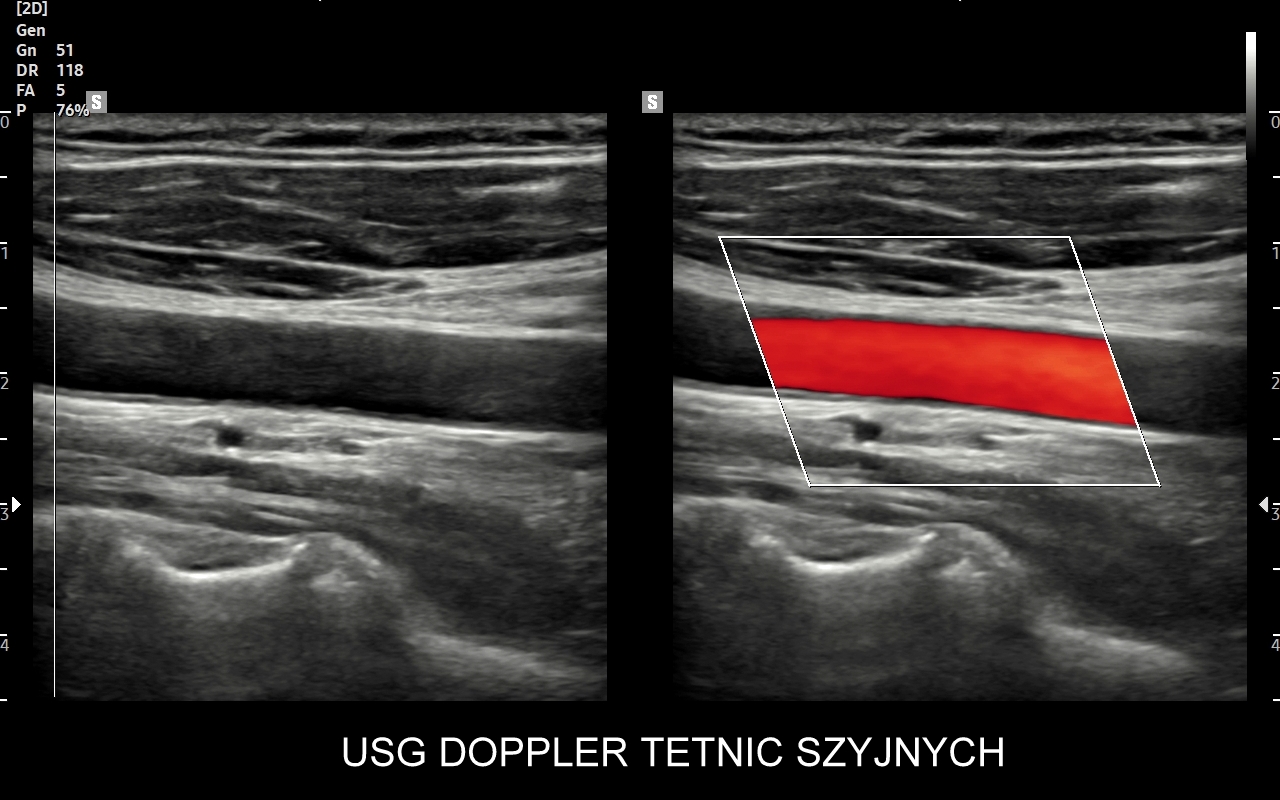

USG tętnic szyjnych i kręgowych

Badanie USG Doppler tętnic szyjnych i kręgowych, określane również jako badanie USG tętnic dogłowowych, to najczęściej wykonywane badanie diagnostyczne w układzie tętniczym. Wynika to z faktu, iż wymienione naczynia doprowadzają krew do jednego z najważniejszych organów człowieka, tj. mózgu, a choroby lokalizujące się w tętnicach dogłowowych mogą być źródłem różnorodnych objawów neurologicznych począwszy od zaburzeń pamięci i widzenia, poprzez bóle i zawroty głowy, aż do zgonu na tle nagłego udaru niedokrwiennego. W trakcie standardowego badania USG tętnic dogłowowych oceniane po obu stronach są tętnice szyjne wspólne, wewnętrzne, zewnętrzne oraz tętnice kręgowe. Badanie niejednokrotnie rozszerza się o specjalistyczną ocenę USG łuku aorty, USG tętnic podobojczykowych, USG tętnic skroniowych, czy o badanie USG Doppler przezczaszkowy.